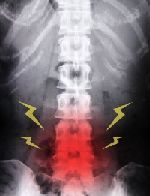

8月27日 脊柱管狭窄症 葛飾区青戸 たじり整骨院

紹介で当整骨院に通われた60代男性の患者さんです。

某大学病院で重度脊柱管狭窄症と診断され手術を勧められたそうです。

5分も歩くと歩けなくなる、特に腰から両下肢にかけて症状が強くでるそうです。

検査をしてみると、全身の歪みがありました。

首、肩、背中の張りが強く、特に下半身の緊張がかなりありました。

動きの検査などもしてみて、脊柱管狭窄症と思われる以外にも気になるところがありました。

⇒脊柱管狭窄症とは

オステオパシー、ワールドセラピーシステム(WTS)整体などの施術を行い3ヶ月ほどで、症状はかなり改善してきました。

6ヶ月程で全ての症状はほとんどでなくなりました。

駅から自宅まで歩いて帰れるようになりました。

再び大学病院で検査をしたところ、やはり重度脊柱管狭窄症と言われてがっかりしたそうです。

今では毎週家族で一時間以上ウォーキングをしているそうです。

一時間以上歩いても全く平気で、家族の誰よりも早く歩けるので、奥さんに「本当に脊柱管狭窄症なの?」と言われるそうです。